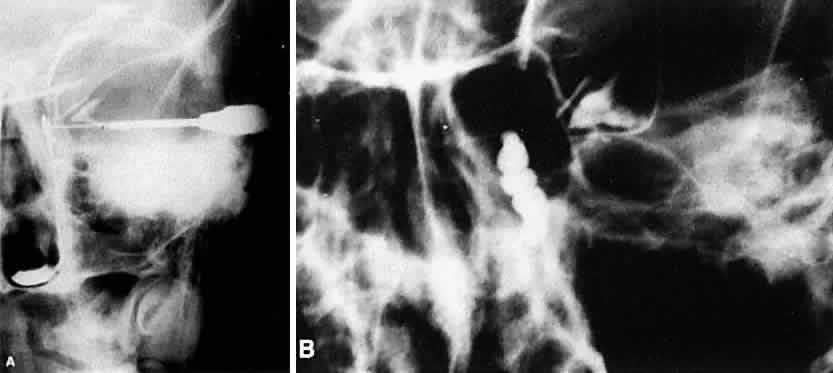

Dacryocystography, a technique of anatomically displaying the lacrimal sac and ducts by radiopaque dye, was popularized by Milder and Demorest.63 Radiopaque dye is forcibly injected into the lower canaliculus with a syringe, using a lacrimal cannula or a polyethylene tube. Radiographs in the Caldwell and lateral views are taken. Preliminary syringing of the lacrimal sac with saline before injection of the dye should be performed to cleanse the sac and make room for the dye. Dye should be wiped from the lids before x-ray films are taken to avoid obscuring details, and oblique views instead of lateral views should be obtained radiologically if both sacs are to be x-rayed simultaneously. Dacryocystography may be helpful in showing the size of the sac, the relationship of the ethmoidal air cells to the lacrimal sac, filling defects in the sac such as lacrimal casts or lacrimal sac tumors, diverticula and fistulas of the sac, and possibly the exact level of the stricture within the lacrimal sac or nasolacrimal duct (Fig. 12). Dacryocystography is not a test of function, because the dye is forcibly injected, and it is of no value in diagnosing a functional block. It does not demonstrate the canaliculi and, in fact, in most cases bypasses them completely. Most surgeons believe that conventional dacryocystography does not alter the clinical approach to patients or affect the therapeutic decisions that can be made at the time of surgery, because a high index of suspicion for unusual conditions may already be present from other clinical signs. Dacryocystography can, however, be a useful adjunct for confirmation of a problem.

Fig. 12. A. Normal dacryocystogram (Waters' view roentgenogram). The contrast dye fills the normal left lacrimal sac and nasolacrimal duct. Contrast dye collects along the floor of the nose as it exits from the distal nasolacrimal duct. B. Abnormal dacryocystogram. Contrast dye fills a grossly enlarged lacrimal sac with ectasias in a patient with a functional nasolacrimal duct obstruction.